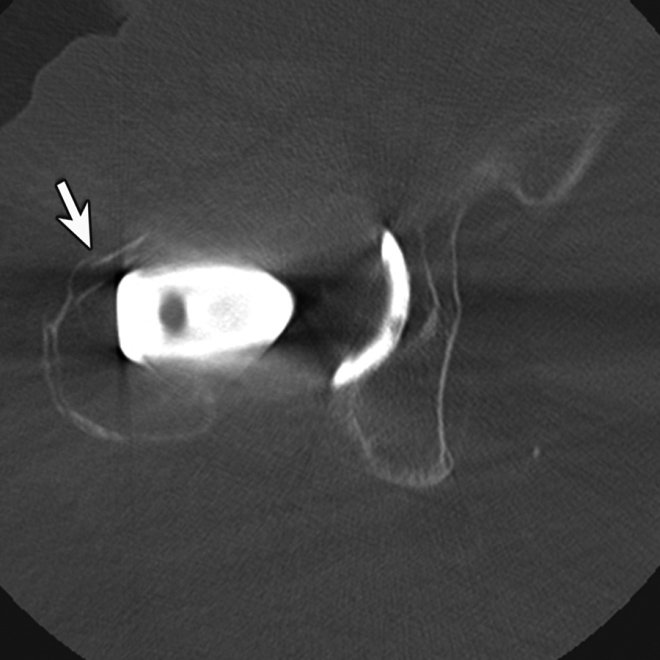

While periprosthetic fractures may occur acutely or chronically following fracture fixation or arthroplasty, CT may be more beneficial in the chronic setting to accurately assess the exact extension of the fracture and residual bone volume, which may be obscured by overlying surgical hardware (Figure 8) (Ohashi, 2009). Further, CT may be helpful to better assess multiple overlapping screws or complex hardware before surgical intervention. Cross-sectional imaging with CT or MRI may also be useful for the assessment of incomplete or stress fractures resulting in chronic post-operative pain.

Periprosthetic Fracture. (A) Coronal multiplanar reformation and (B) axial CT image of the right hip demonstrate radiographically occult non-displaced periprosthetic fracture involving the greater trochanter (arrow)